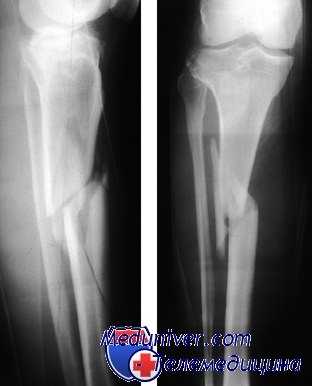

КТ коленного сустава и голени. Оскольчатый перелом большеберцовой кости в верхней трети диафиза (красная стрелка), перелом головки малоберцовой кости (синяя стрелка), перелом латерального мыщелка большеберцовой кости (зеленая стрелка).